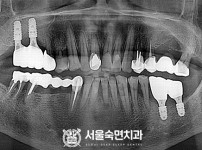

임플란트-전후사진2

임플란트-전후사진3

치과를-선택할-때-꼭-확인하세요-서울숙면치과-임플란트-전후사진